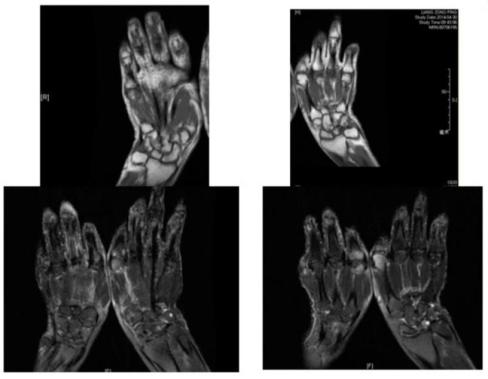

图4:影像学检查苏茵主任提示,虽然我们能够从11年到14年的影像学资料上看到,该患者近端指间关节处有明显的关节破坏,但这种破坏跟我们以往看到类风湿关节炎的虫噬样改变是不一样的。

图5:患者MRI表现,无骨端骨质舒松,与常见的类风湿关节炎不同患者的影像学表现均与以往类风湿关节炎的常见表现不同,又对患者进行了超声检查。